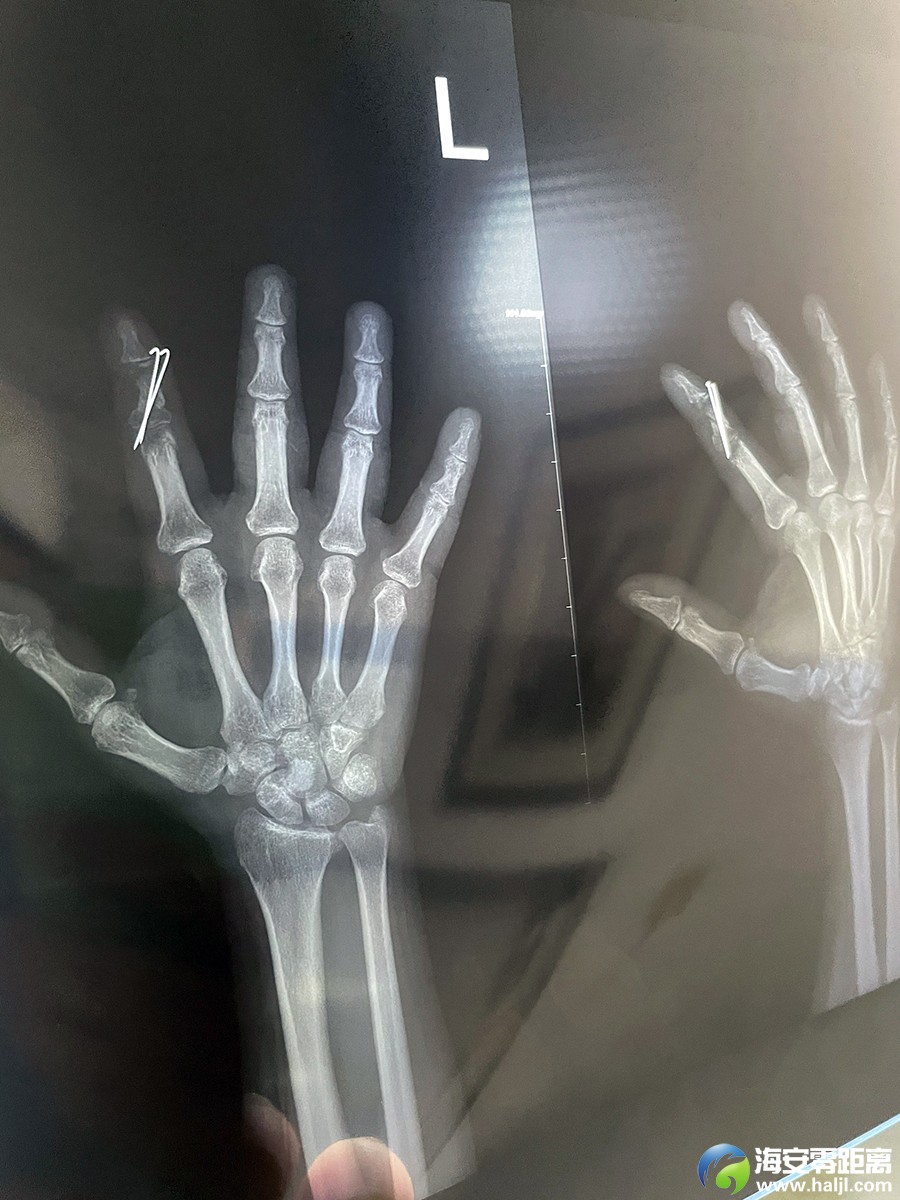

本人身份证号320621198401318710,保证所述为实,负法律责任。二里新村9栋2单元403为本人楼上住户,其卧室老床异响严重,影响本人休养作息,因粉碎性骨折休养期间得不到静养,本人骨折后恢复很不理想,后遗症严重,骨折部位错位变形肿胀未能恢复,严重影响本人找工作,多次跟楼上交涉寻求减少噪音,均受到蛮横无理对待。该楼上住户行事为人莽撞,曾开电瓶车冲撞本人,此事有报警后的出警记录为证,其母知晓本人骨折居家疗养,故意制造噪音,与其子拒不配合本人降低噪音的合理诉求,涉嫌故意人身伤害。二里社区面对此蛮横无理居民,调解无力,故本人公开向社会曝光并求助,合理诉求如下:一是赔偿本人骨折居家疗养期间因楼上噪音导致恢复不佳(有片子为证)影响就业的精神损失费,二是把卧室内噪音源老床加以修理或进行更换,以及保证在本人骨折居家疗养恢复期间,减少人为制造噪音。以下是403住户蛮横无理视频证据及业主群里该403住户承认制造噪音且拒不改正的相关证据。顺提,之前403住户漏水导致本人家中热水器受腐蚀损坏,也未曾赔偿本人家中所受损失。